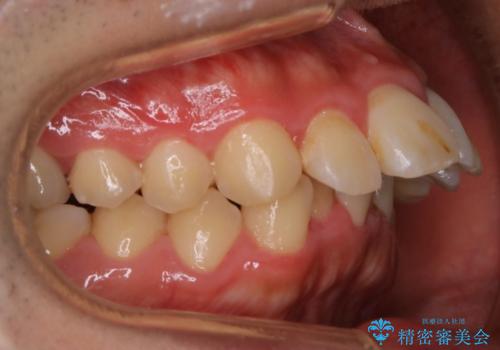

出っ歯、ガタつきの改善 ワイヤー矯正治療

- 上顎前歯の突出感と下顎前歯のガタつきが主訴で来院されました。

出っ歯とガタつきの改善を行うには抜歯が必要と診断し、上下左右第一小臼歯を抜歯する計画を立てました。